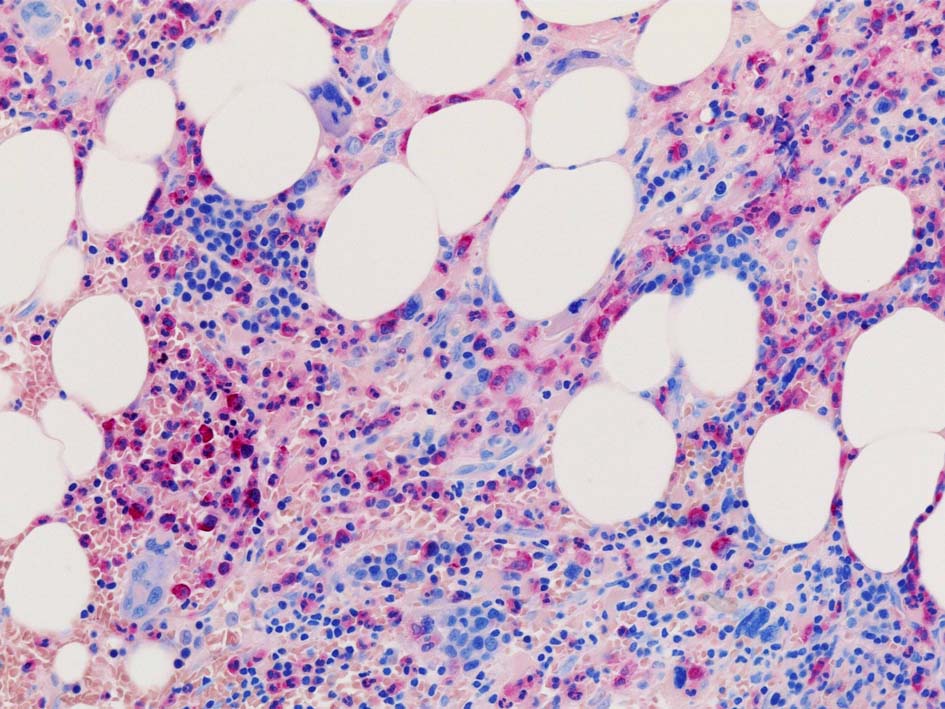

Case01; Meylofibrosis, overt fibrosis

77year-old female. 40歳時polycythemia veraと診断されていた.

[注] この症例は詳細は不明であるが, 過去にPVと診断されているため, PVに伴う二次性のmyelofibrosisの診断になる.

黒染する弾性線維の増生のほか, 赤く染まる膠原線維の増生が確認される. MF-2 fibrosis. 鍍銀染色の核染色をすると膠原線維の赤染がわからなくなるので行わない.